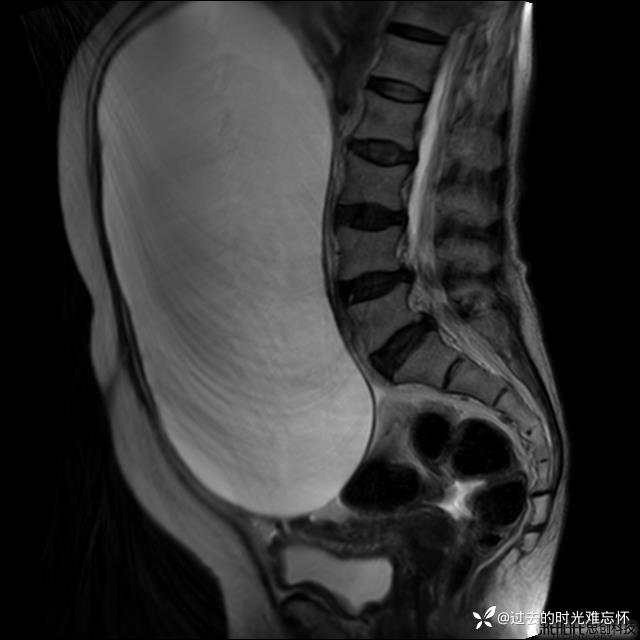

患者性别:女

患者年龄:65岁

主诉: 发现腹部隆起半年余。无其他明显不适。

浆液性囊腺瘤 (22)